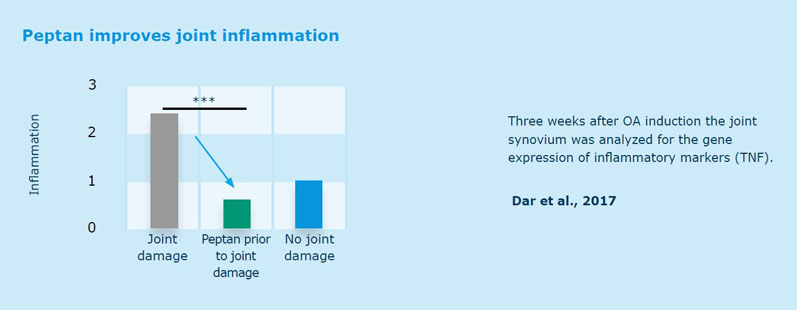

With regard to joint health, an in vivo study found that a daily dose of Peptan before cartilage damage resulted in cartilage preservation (Figure 1) and reduced inflammation (Figure 2) in mice, whereas in a randomised, placebo-controlled, double-blind clinical trial, elderly women with mild joint discomfort reported a significant reduction of painful symptoms, such as stiffness and pain, after oral intake of Peptan.6,8

These scientific findings showed this solution’s ability to increase the production of cells responsible for the building and maintenance of the cartilage matrix after just 3 weeks.

Figure 2: Peptan reduces inflammation in mice